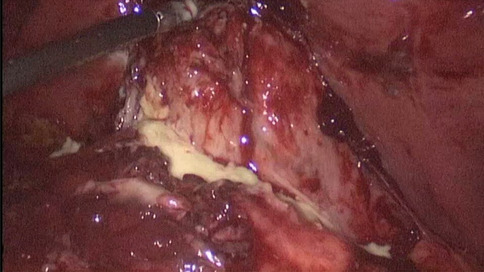

Result: The comparative analysis of the data shows a decrease in the number of presentations in ESU of AC cases during the pandemic, compared to the previous year, most often due to patients' fear of contacting the virus in the hospital environment. The median time between the onset of symptoms and the presentation in the ESU: 2020 – 14 days, 2019 – 5 days. Forms of moderate and severe AC predominated in the pandemic: GradeI—14.28%; GradeII—57.14%; GradeIII—28.57%. In 2019 GradeI—66.39%, GradeII—27.73%, GradeIII—5.88%. Laparoscopic cholecystectomy was attempted for all patients from the beginning, but the complications identified during surgery and severe forms led to a conversion rate in 2020 of 14.28%, compared to 5.88% in 2019. The severity of the cases is also observed in the postoperative complications encountered (perihepatic abscess Fig. 2. Figure 2, wound infection, bile leak; 2019—5.04%, 2020—23.21%), which required surgical reinterventions to solve them (2019: 2.52%, 2020: 10.71%). The number of deaths was significantly higher in 2020 (5.35%), compared to 2019 (0.84%).